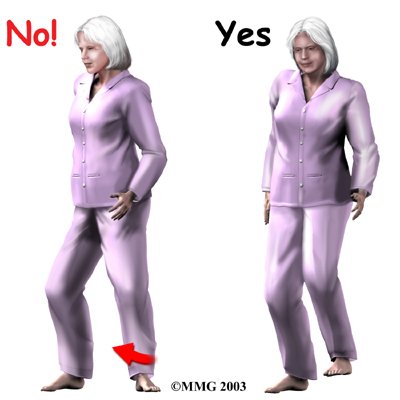

- Don't twist your body away from your operated hip. This means don't stand with your toes pointed out. Keep the toes of your affected leg pointed forward when you stand, sit, or walk. If you turn your body away from your surgical hip without pivoting your foot, your hip will be placed in an unsafe position. Remember to lift and turn your foot as you turn.

- Don't twist your body toward your operated hip. This means don't stand pigeon-toed. Keep the toes of your affected leg pointed forward when you stand, sit, or walk. If you turn your body in the direction of your surgical hip without pivoting your foot, your hip will be placed in an unsafe position. Remember to lift and turn your foot as you turn in the same direction as your surgical hip.